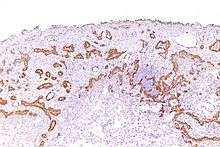

Mesothelioma

Using immunohistochemistry, calretinin can be demonstrated in both benign mesothelium and in malignant mesothelioma[10][11] and can be used to help differentiate different lung tumours.[12] Antibodies to calretinin can also be used to distinguish between different types of brain tumour, demonstrating only those with neuronal rather than glial, differentiation.[13] Furthermore, the essential function of calretinin in mesothelioma cell lines has been demonstrated in vitro and may be an interesting target for therapeutical approaches.[14]